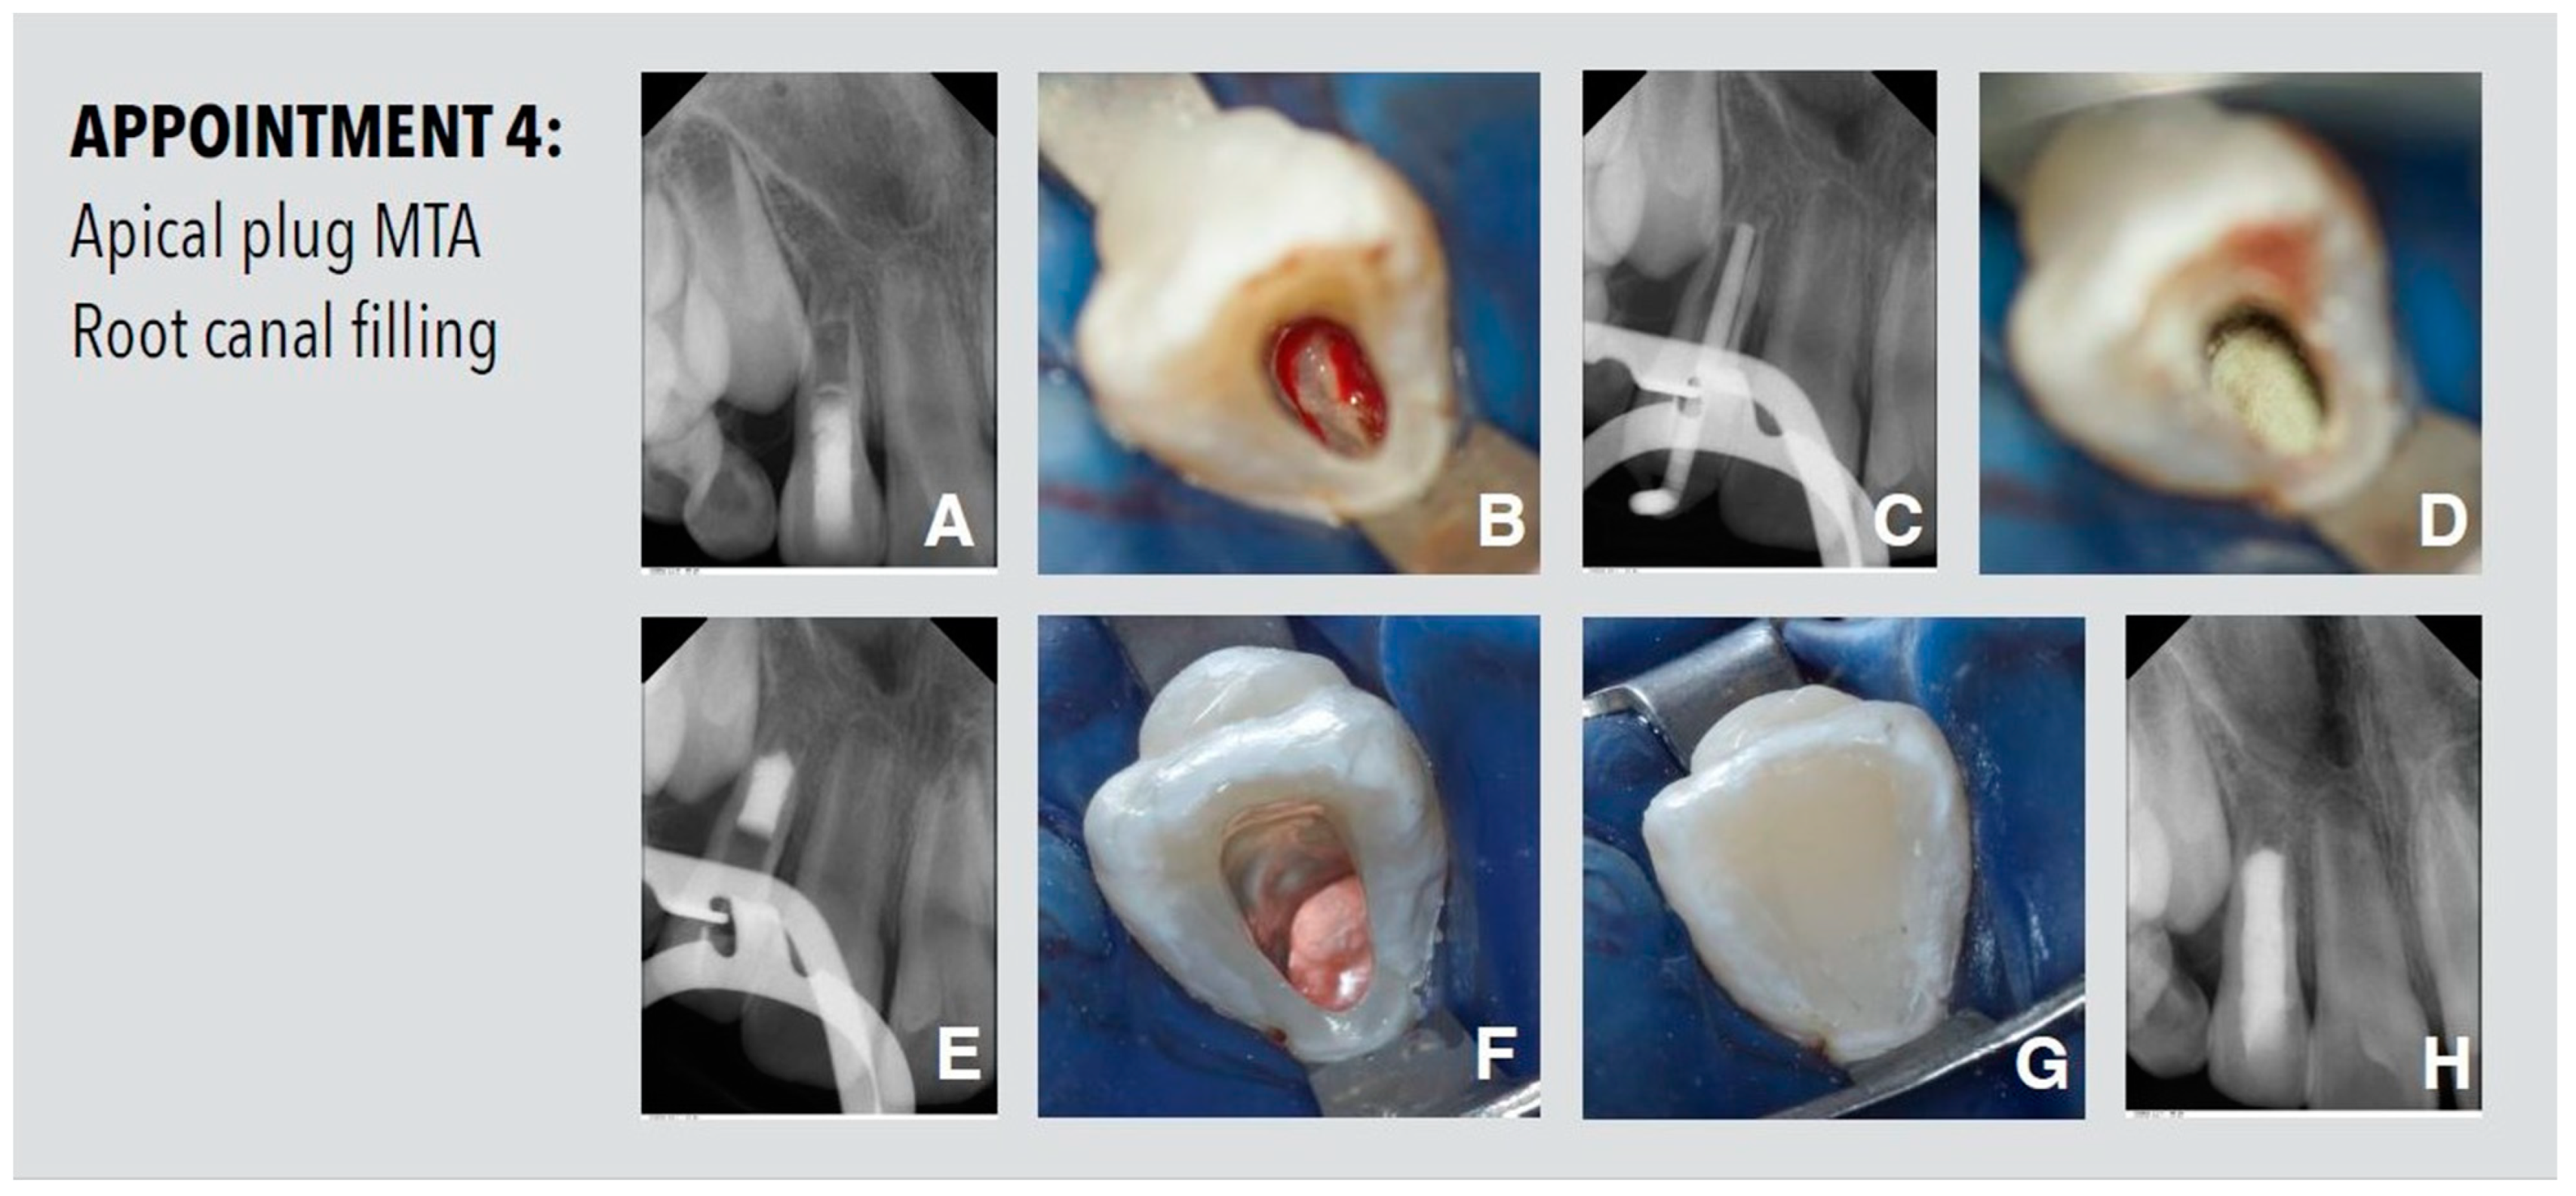

2.4. Appointment 4

After ten weeks, a hard tissue barrier could be detected at the apex of the root on the periapical radiograph (Figure 4). After irrigation and removal of calcium hydroxide remnants from the root canal, the incomplete apical hard tissue barrier was clearly visible under the operating microscope. The root canal was then dried using paper points and an apical MTA (ProRoot MTA; Dentsply Sirona, Konstanz, Germany) plug of 5 mm was placed by using an MTA gun (MAP System, Produits Dentaires SA, Vevey, Switzerland) and compacted with large paper points. The remaining canal space was obturated using a warm vertical gutta-percha and sealer up to 3 mm below the CEJ. The remainder of the root canal and access cavity was restored with a bonded composite material.

Figure 4.

Procedures performed at the fourth appointment. (A) Periapical radiograph. (B) Hard tissue barrier was clearly visible under the operating microscope. (C) Radiographic working length determination with gutta-percha point. (D) Apical plug with MTA. (E) Radiologic view of the apical MTA plug up to the apical hard tissue barrier. (F) Obturated root canal using a warm vertical gutta-percha and sealer up to 3 mm below the cement–enamel junction (CEJ). (G) Sealed cavity with bonded composite resin. (H) Periapical radiograph of the root filled tooth.